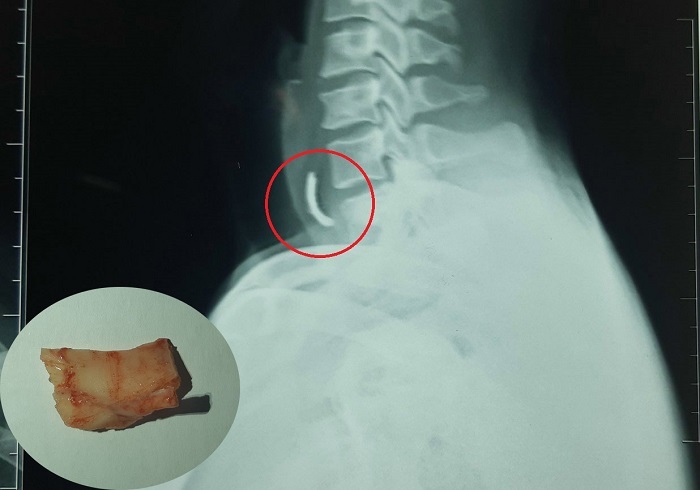

Trước đó, chiều 14/6, khoa Cấp cứu của bệnh viện tiếp nhận anh N. trong tình trạng đau nhức, mắc nghẹn ở cổ họng. Các bác sĩ tiến hành chụp X-quang phát hiện, anh N. mắc một mảnh xương ngang thực quản.

Bằng phương pháp nội soi mềm đi qua đường miệng vào thực quản, bác sĩ đã gắp được mảnh xương kích thước 2,5x1,5 cm trong thực quản bệnh nhân.

Mẫu xương mắc ngang thực quản bệnh nhân được bác sĩ lấy ra